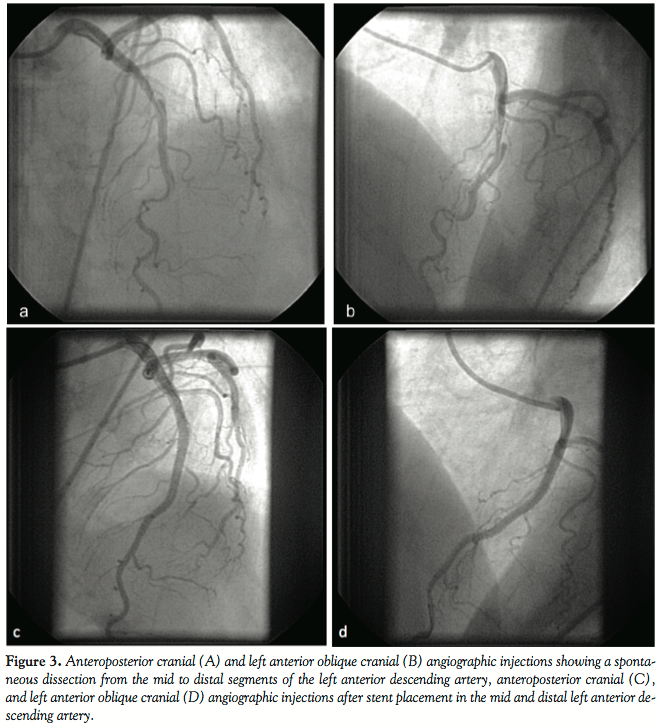

The patient underwent urgent coronary angiography, which revealed normal right and left circumflex coronary arteries. The left anterior descending artery had a long dissection in the mid-segment, which contained thrombus (Figures 3A and 3B). After a prolonged discussion with the patient’s family, the decision was to proceed with coronary intervention due to the ongoing symptoms and thrombotic nature of the dissection. The lesion was successfully treated with balloon angioplasty followed by placement of 3 drug-eluting stents (Xience), resulting in TIMI-3 flow (Figures 3C and 3D).